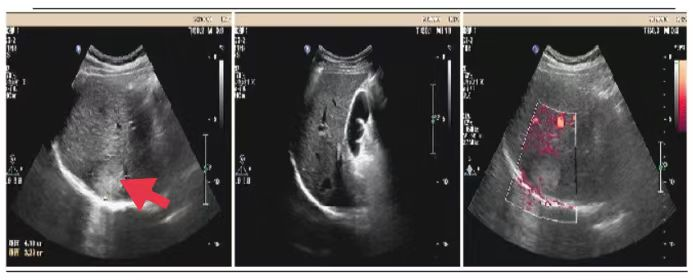

05、**女士,73岁

于2023年10月14日在邢台仁泰体检部体检,子宫附件彩超检查提示: 子宫切除术后,盆腔内可见大小约9.2*6.7cm囊实性包块,边界欠清晰,形态欠规整,CDFI;周边可见点状血流信号。诊断: 盆腔内囊实性包块。建议客户到三甲医院进一步检查。2023年10月19日跟踪回访,客户家属告知,确诊盆腔肿瘤,住院准备手术。